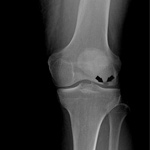

Knee Arthritis

The joint surface is covered by a smooth articular surface that allows pain-free movement in the joint. Arthritis is a general term covering numerous conditions where the joint surface or cartilage wears out. This surface can wear out for several reasons; often the definite cause is not known. Arthritis often affects the knee joint. When the articular cartilage wears out, the bone ends rub on one another and cause pain. The most common type of arthritis is osteoarthritis. It occurs with aging and use.

Knee Osteoarthritis

Osteoarthritis also called degenerative joint disease, is the most common form of arthritis. It occurs most often in older people. This disease affects the tissue covering the ends of bones in a joint (cartilage).In a person with osteoarthritis, the cartilage becomes damaged and worn out causing pain, swelling, stiffness and restricted movement in the affected joint. This condition most commonly affects the joints in the hips, knees, hands, and spine. Rarely, the disease may affect the shoulders, wrists, and feet.